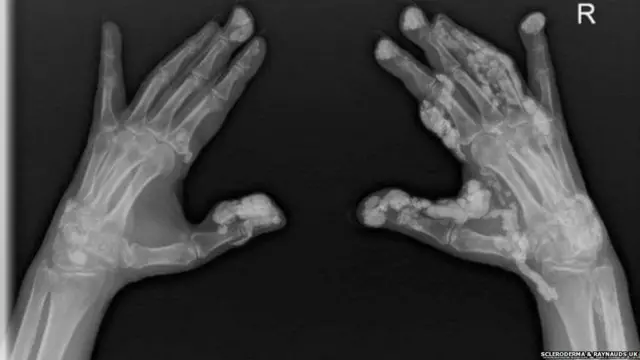

ਤਸਵੀਰ ਸਰੋਤ, SCLERODERMA & RAYNAUDS UK

- ਇਹ ਇੱਕ ਲਾਈਲਾਜ ਬਿਮਾਰੀ ਹੈ, ਜਿਸ ਵਿੱਚ ਸਰੀਰ ਦੇ ਸਿਹਤਮੰਦ ਟਿਸ਼ੂਆਂ 'ਤੇ ਅਸਰ ਪੈਂਦਾ ਹੈ। ਇਸ ਕਰਕੇ ਚਮੜੀ ਦਾ ਹਿੱਸਾ ਸਖ਼ਤ ਹੋਣ ਲੱਗਦਾ ਹੈ। ਇਹ ਇਸ ਬਿਮਾਰੀ ਦਾ ਪਹਿਲਾ ਲੱਛਣ ਹੈ।

- ਠੰਡ ਵਿੱਚ ਹੌਲੀ-ਹੌਲੀ ਉਂਗਲੀਆਂ ਅਤੇ ਪੈਰ ਦੇ ਅੰਗੂਠੇ ਚਿੱਟੇ ਹੋਣ ਲਗਦੇ ਹਨ, ਜੋ ਬਾਅਦ 'ਚ ਸਖ਼ਤ ਹੋ ਜਾਂਦੇ ਹਨ।

- ਸਕਲੇਰੋਡਰਮਾ ਦੀ ਇੱਕ ਕਿਸਮ ਹੈ, 'ਸਿਸਟਮਿਕ ਸਕਲੇਰੋਸਿਸ', ਇਸ ਨਾਲ ਸਰੀਰ ਦੇ ਅੰਦਰਲੇ ਅੰਗਾਂ ਖਾਸ ਕਰਕੇ ਫੇਫੜਿਆਂ 'ਤੇ ਅਸਰ ਪੈਂਦਾ ਹੈ।